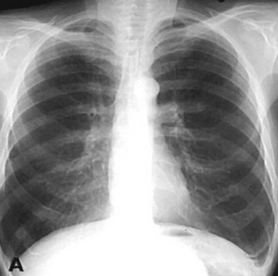

Rx toracică, incidență P-A

DESCRIERE:

DX: emfizem pulmonar

DD: